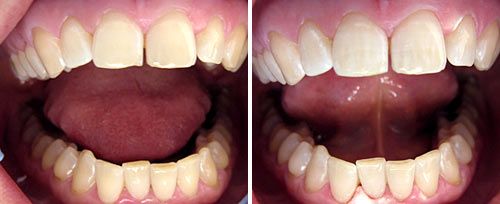

Tooth Whitening

Courtesy of: Jugoslav Jovanovic, DDS

Laser source: Er:YAG (2940 nm)